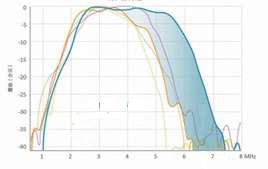

Xcen Probe Technology

The Xcen high-frequency wideband probe transmits at up 16 MHz and provides clearer images of subtle variations in tissue, which allows lesions to be diagnosed earlier.